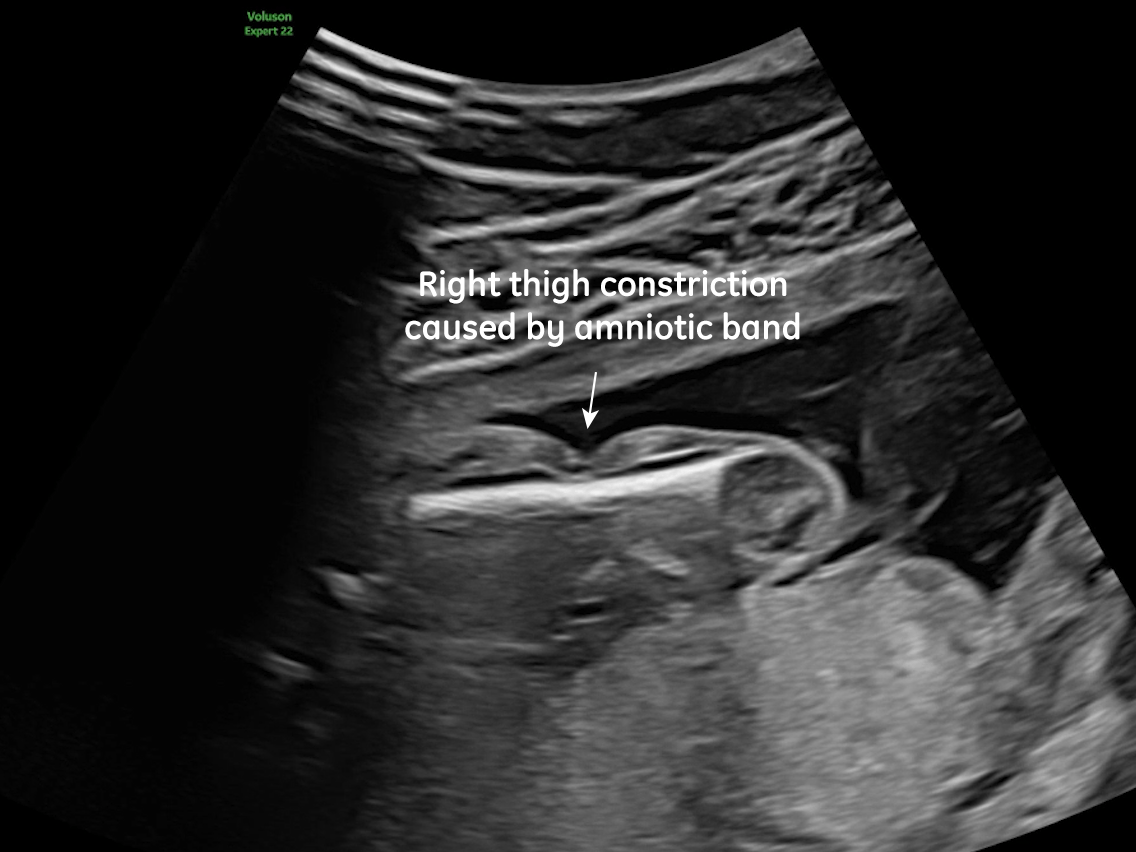

Club foot

Image 4 Club foot

• Bilateral club feet

Prenatal ultrasound imaging shows thin echogenic bands attaching to both the uterine wall and associated fetal structures. The bands themselves can be difficult to detect, hence the visualization of bands is not required to suggest the diagnosis. Random anomalies that do not follow a pattern should lead the clinician to suspect amniotic band sequence and prompt close evaluation for a causative band [5, 6]. The defects resulting from the bands are categorized into various categories: neural tube-like defects, craniofacial anomalies, limb anomalies, abdominal and thoracic wall defects, and visceral anomalies [7, 8]. The most common findings are those caused by constriction rings in the limbs, which are present in at least 80% of cases. They may vary in depth, involving only the skin, to involving bone and causing edema of the distal limb, extremity asymmetry, pseudosyndactyly, or amputation of limbs or digits [8]. Histologically, constriction bands are composed of fibrous tissue containing fibroblasts covered by squamous cells, which may make them inelastic and produce a ligature effect [9]. Clubfoot deformity of the lower extremity is found in up to one third of cases, probably secondary to the presence of oligohydramnios if there is loss of amniotic fluid [6].